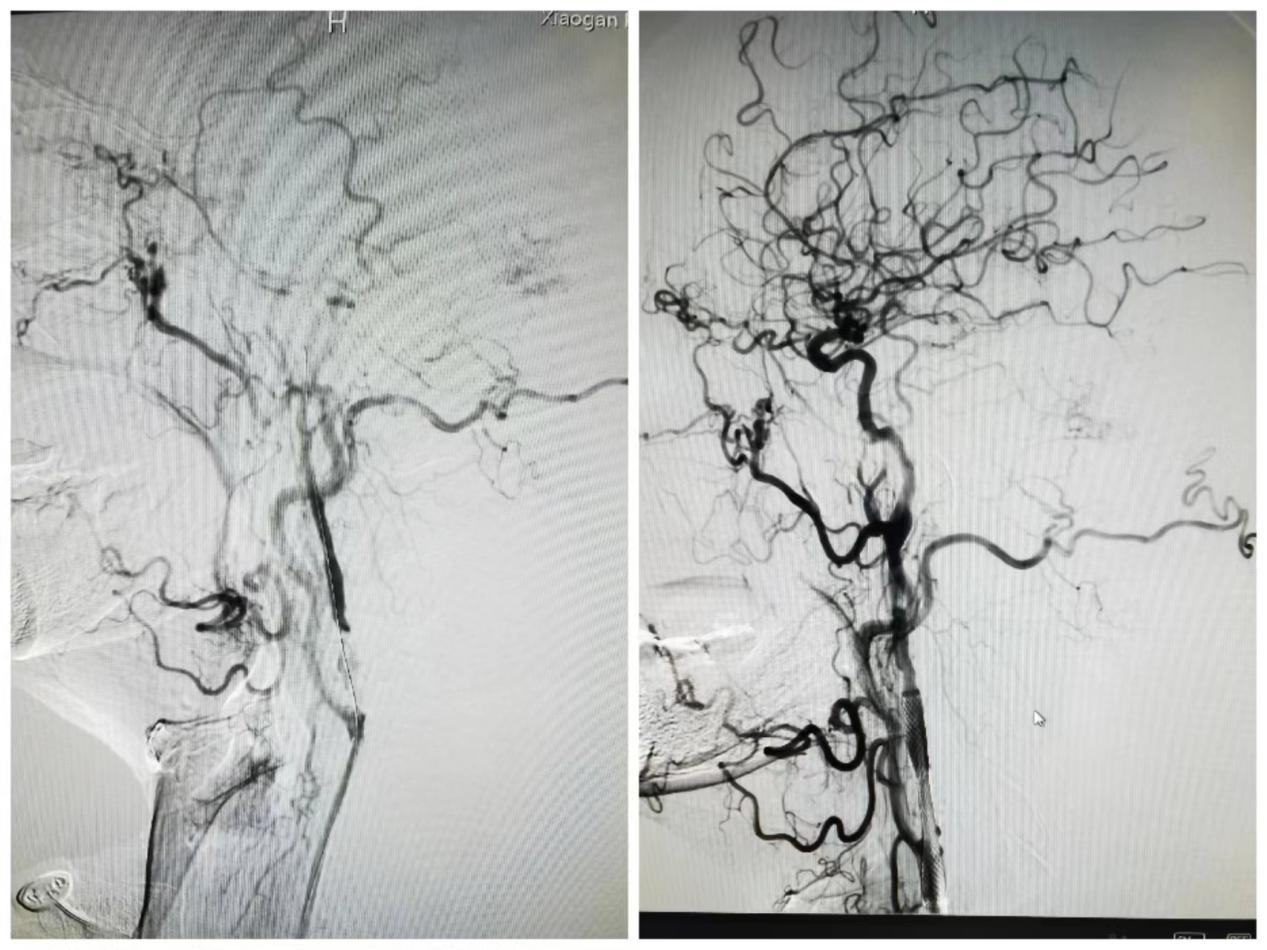

10月13日,孝感市第一人民醫院神經內科醫學博士許賢平精準、嚴謹評估,并組織神經內科醫生團隊進行術前討論,大家激烈發言,在征得患者及家屬同意后,最終決定14日為患者開展腦血管介入頂尖技術——開通頸內動脈次全閉塞術后支架植入,打通大腦“生命線”。

10月14日9:00,許賢平博士和科室副主任李勇超秉持以精湛的醫療技術、良好的醫德醫風,為患者提供更加專業、優質、高效的醫療服務。最終確定為患者進行頸內動脈閉塞開通術+支架植入術,患者黃大爺的顱內半球成功恢復了循環供血,殘余狹窄小于30%。